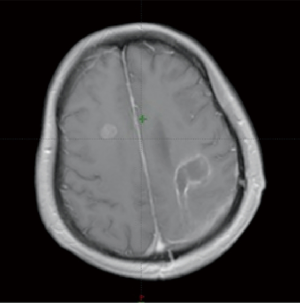

A 51-year-old female patient presented with right-limb paralysis as onset. In June 2016, T1-enhanced magnetic resonance imaging (MRI) of the head showed an abnormally enhanced occupancy signal in the left parietal and right frontal areas. Moreover, in July 2016, the left parietal lesion was surgically removed and pathologically confirmed as GBM (World Health Organization, grade IV). A postsurgery Gd-enhanced T1-weighted MRI was performed, as shown in Figure 1. She then received a postoperative 6-week intensity-modulated radiation therapy (IMRT) during which temozolomide [75 mg/m2, once daily (qd)] chemotherapy was synchronized. The IMRT was arranged as follows. In the first phase, radiation was given 2 cm outside the range of fluid attenuated inversion recovery (FLAIR) abnormal signal at an exposure extent of 40 Gy/20 f. This was followed by an MRI re-examination with a simultaneous integrated boost technique conducted for a right frontal lesion in the range where the T1 was enhanced. Moreover, the left parietal lesions within the surgical cavity were irradiated at 24 Gy/10 f, with simultaneous radiation to the area with FLAIR abnormal signal at 18 Gy/10 f. The dose distribution is shown in Figure 2. After 3 weeks of concurrent chemoradiotherapy, the patient was admitted to the hospital again due to severe headache and frequent seizures. No significant improvement was observed in the symptomatic treatment therapy of mannitol plus dexamethasone for 1 week. Enhanced T1-enhanced MRI scan showed that the abnormally enhanced range of the original left parietal and right frontal lesions significantly increased compared with that before radiotherapy, as shown in Figure 3. After fusion of the T1-enhanced MRI with the IMRT dose distribution image, the right frontal and left parietal abnormality enhancement signals were found to lay entirely within the 90% prescription dose field, as shown in Figure 4. The postoperative molecular pathological results showed that the O6-methylguanine-DNA methyltransferase (MGMT) promoter methylation was positive in the left parietal lesion. After a multidisciplinary team discussion, the patient was diagnosed with pseudoprogression after chemoradiotherapy. Continuous temozolomide monotherapy chemotherapy (250 mg/m2 days 1–5 q28d) was given as originally planned due to the poor result of previous dexamethasone treatment. Apatinib, as the concurrent treatment therapy, was given to the patient at a dose of 500 mg qd. During this treatment, symptoms of headache and rapid onset of seizures disappeared immediately. After 1 week of treatment with apatinib, MRI examination showed that the scope of the original abnormally enhanced signal was significantly reduced and the peripheral edema was alleviated compared with the images before treatment, as shown in Figure 3. The patient was treated with apatinib (500 mg qd) for 8 weeks, during which the drug was well tolerated and the patient did not show serious adverse effects to apatinib therapy. MRI scan showed no significant abnormally enhanced signal in the area of the primary lesion 14 months after the surgery (in September 2017), supporting the diagnosis of pseudoprogression after initial radiotherapy and chemotherapy, as shown in Figure 3.